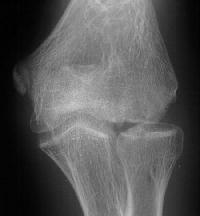

Plain films show humeral osteophytes and posttraumatic changes of the capitellum and radial head.

MRI shows an osteochondral sequestrum of the anterior capitellum: